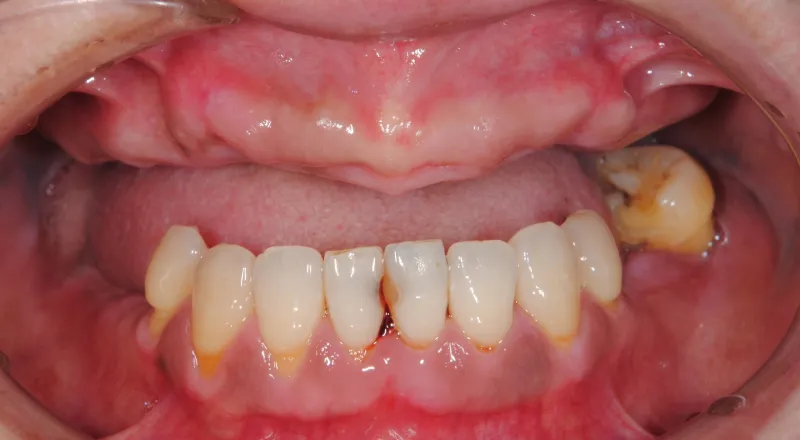

| 主訴 | 歯が抜けている。 入れ歯のところをインプラントしたい |

|---|---|

| 診断名 | 歯の欠損、義歯不適合 |

| 年齢・性別 | 63歳・男性 |

| 治療期間・回数 | 1年3ヶ月・33回 |

| 治療方法 | 精密根管治療、ジルコニアクラウン、GBR、インプラント、ホワイトニング |

| 費用 | 3,949,000円 最高プラン (費用を抑えたプランも提案可能) |

| 治療上のリスク |

|